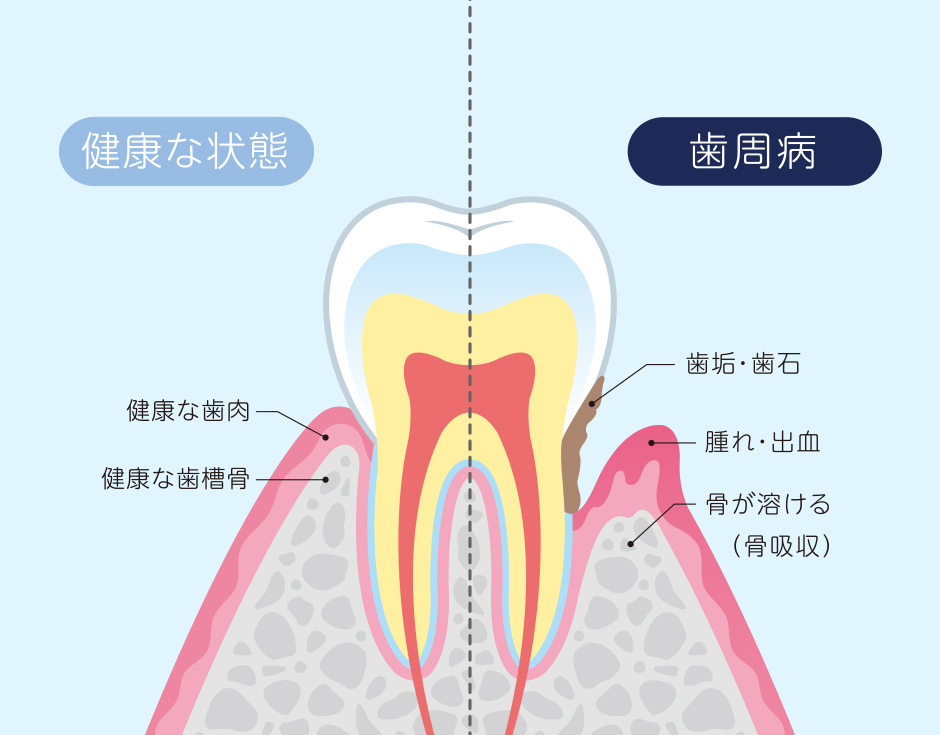

歯周組織が壊されてしまう病気

細菌の感染によって引き起こされる炎症性疾患です。歯と歯肉の間(歯周ポケット)の清掃が行き届かないことで細菌が繁殖して感染します。症状が重くなると、歯を支える歯槽骨が溶けてしまい、最終的には歯が抜けてしまうこともあります。

口腔内で繁殖した歯周病菌は、歯周組織を溶かし、歯を失うリスクを伴いますが、それだけでなく、感染部分から血液にまで細菌が流れることで全身の病気へ影響を及ぼします。

歯周病はその進行度によって、治療が異なりますが、口腔内の細菌の繁殖を抑えるためのメンテナンスによる口腔管理が治療の中心です。重度の場合や経過観察で回復が見られない場合には、歯茎を切開し歯槽骨に付着した汚れやダメージを受けた歯肉などを除去するフラップ手術を行います。